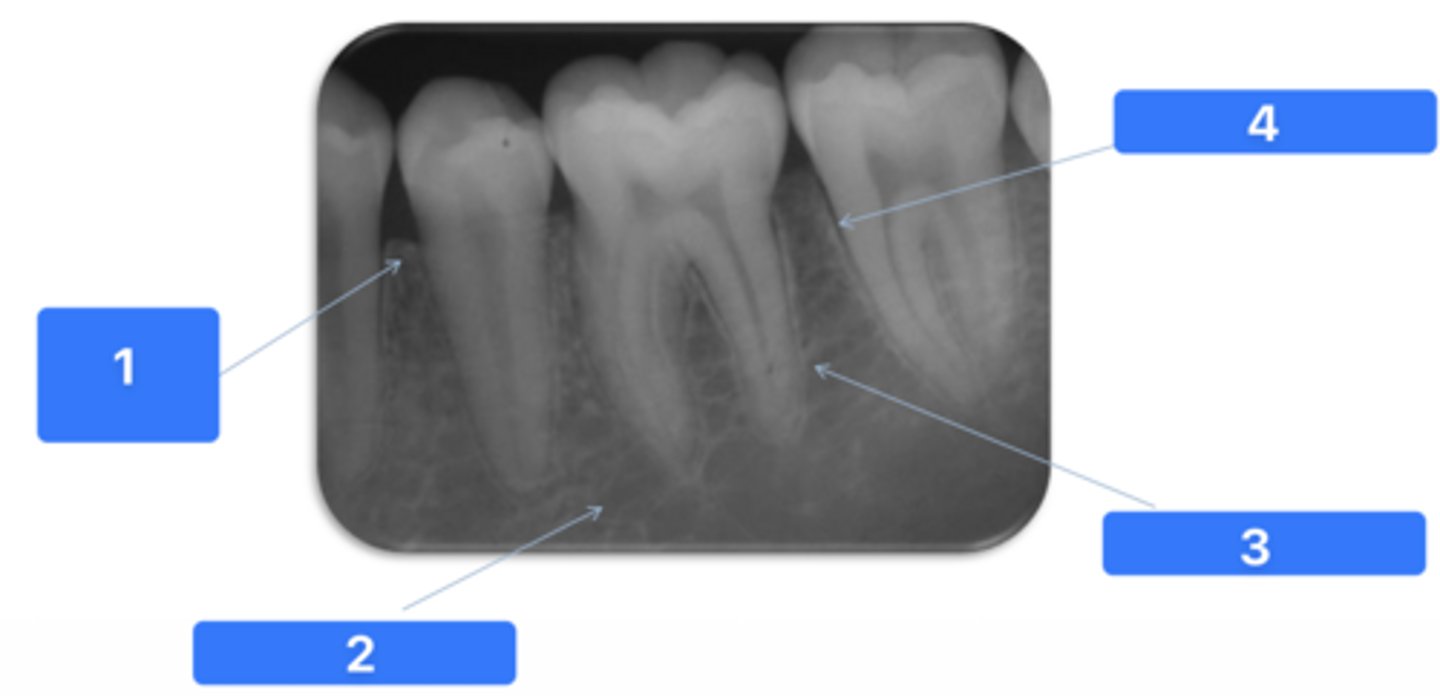

ID the structure at #1:

Alveolar crest

ID the structure at #2:

Medullary bone

ID the structure at #3:

Lamina dura

ID the structure at #4:

PDL space